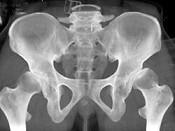

问题 男,23岁,跛行,外展受限,两下肢不等长,结合图像,最可能的诊断是?(?)

选项 A.髋关节中心脱位 B.髋关节后脱位 C.髋关节前脱位 D.先天性髋内翻 E.髋关节结核

答案 B